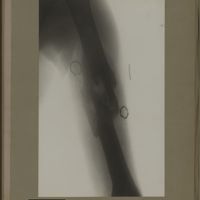

0120 - Page 8 - [Radiographie de l'humérus]0120 - Page 8 - [Radiographie de l'humérus]

0193 - Page 81 - [Radiographie de l'humérus]0193 - Page 81 - [Radiographie de l'humérus]

0195 - Page 83 - [Radiographie de l'humérus]0195 - Page 83 - [Radiographie de l'humérus]